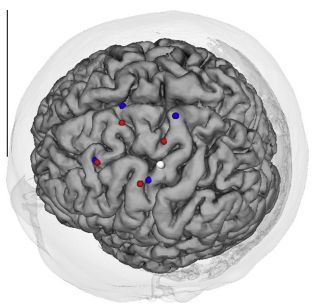

Onishi H, Sugawara K, Yamashiro K, Sato D, Suzuki M, Kirimoto H, Tamaki H, Murakami H, Kameyama S. (2013) Neuromagnetic activation following active and passive finger movements. Brain and Behavior 3:178–192.

Onishi H, Oyama M, Soma T, Sugawara K, Kirimoto H, Murakami H, Kameyama S.(2011) Muscle-afferent projection to the sensorimotor cortex after voluntary movement and motor-point stimulation: An MEG study. Clinical Neurophysiology. 122: 605-610